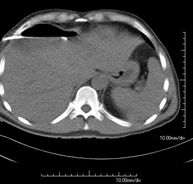

- TC Tórax

Prueba diagnóstica que consiste en obtener imágenes del tórax de alta definición anatómica (pulmones, corazón, mediastino, grandes vasos, caja torácica, etc.) mediante el empleo de un equipo de TC (Tomografía Computarizada). Dichas imágenes se estudian posteriormente en una estación de trabajo que permite reconstrucciones bidimendionales en diferentes planos del espacio y también reconstrucciones 3D (volumétricas). Algunos estudios requieren el empleo de contraste yodado para mejorar la definición de las imágenes.